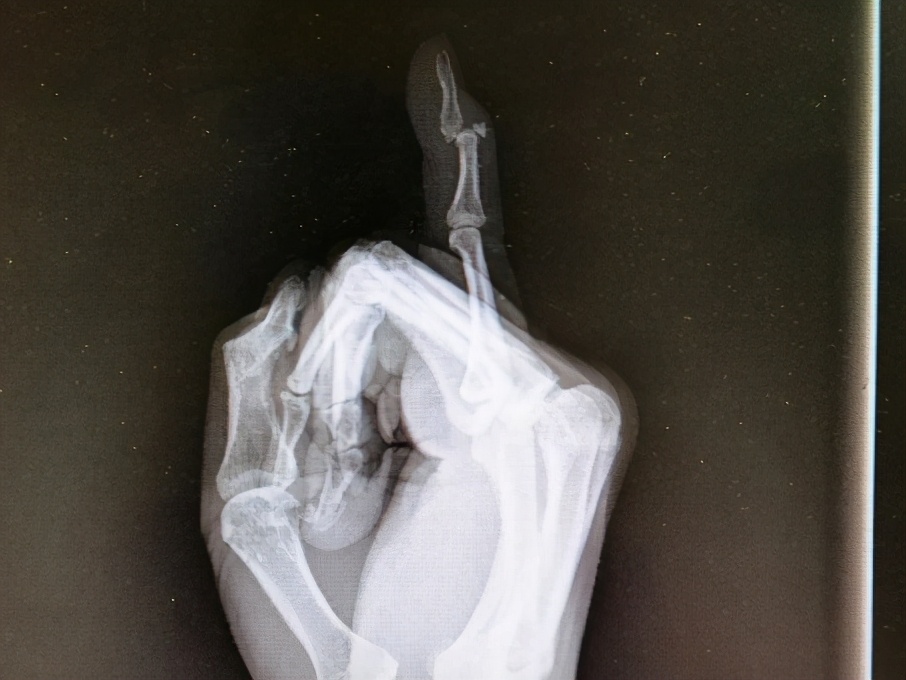

“吃萝卜干”的医学术语是“锤状指”,因为这种手指外伤畸形很像我们日常生活中用的木锤,故而取名为“锤状指”。

在一些意外情况下,手指在伸直位时,受到了突然剧烈的弯曲应力,导致背伸肌腱在止点附近处断裂,常合并止点处的撕脱骨折,从而使最后一节指骨不能伸直,并因为屈指肌腱的牵拉力而使手指末节呈屈曲状,就形成了所谓的“锤状指”。多由于打球前准备活动不足、传接球技术不正确等原因引起。

“锤状指”一旦发生,手指最后一节不能主动伸直,被动可以伸直,但弯曲不受影响,常伴患指发红肿胀。早期患指弯曲程度较轻,若未及时固定,反复活动则可造成弯曲畸形加重,后期瘢痕粘连,就会形成锤状畸形。

首先要去医院行X线检查并确诊是否有骨折,针对早期的和不伴有骨折或轻微无移位骨折的“锤状指”,优先选择保守治疗,将患指用夹板、支具或石膏固定在轻度背伸位,使得撕脱肌腱和指骨基底保持接触,固定时间约 4-6周。